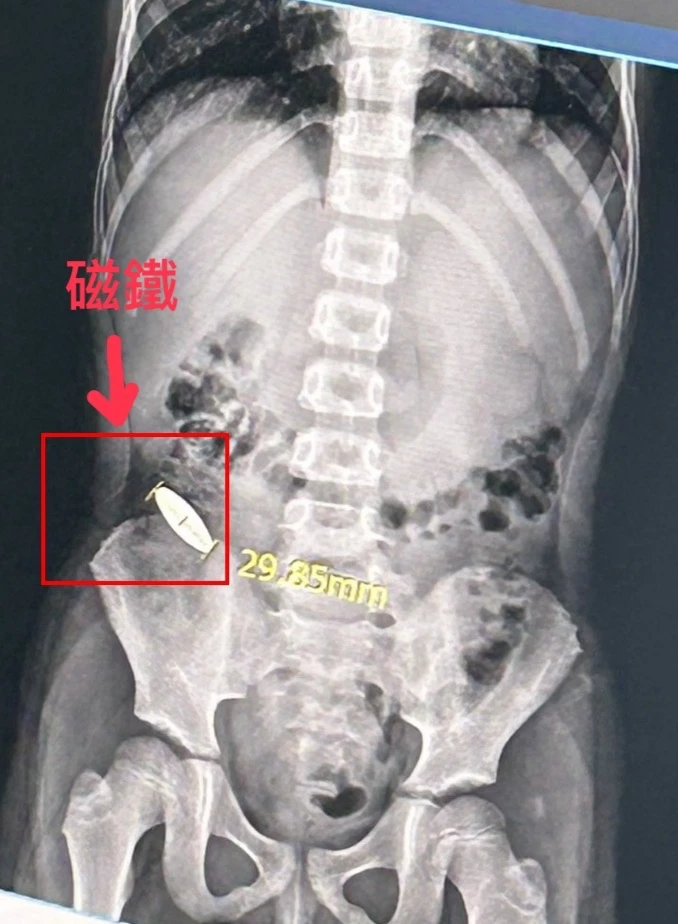

教育局說,針對吞食磁鐵異物男童,目前已由醫院醫師評估並開立軟便劑,協助異物自然排出體外。但至今天中午為止,磁鐵仍在腸中,尚未自然排出。